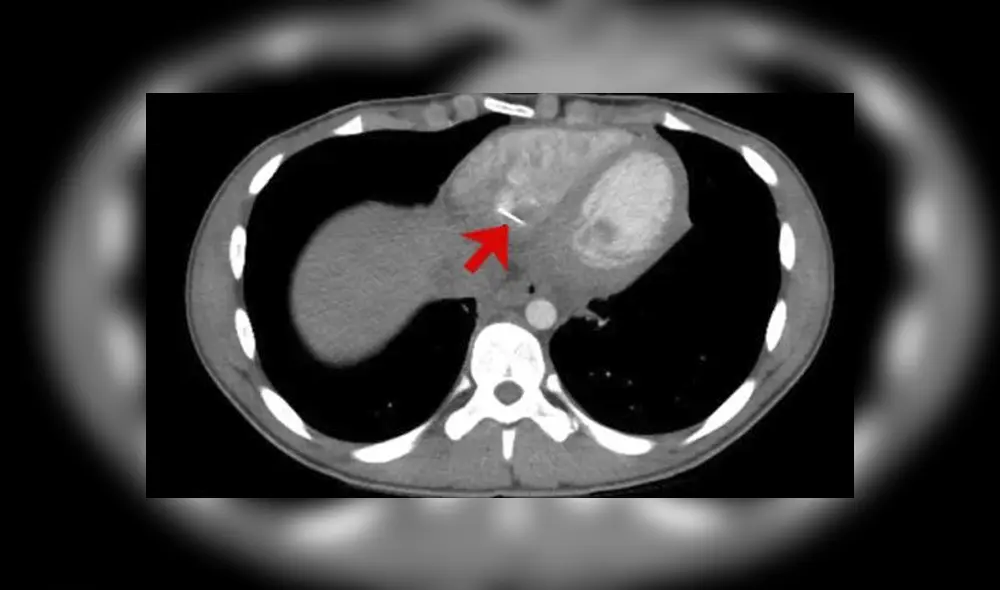

Los resultados obtenidos no resolvieron el misterio del dolor, por lo que decidieron realizar una tomografía computarizada donde finalmente se reveló que en la parte inferior derecha de su corazón tenía alojado un objeto metálico punzante.

De acuerdo a la investigación realizada por los especialistas de la Facultad de Medicina de la Universidad de Massachusetts, Estados Unidos, el adolescente de 17 años tragó sin darse cuenta un alfiler de unos 3,5 centímetros que recorrió su cuerpo hasta el corazón.